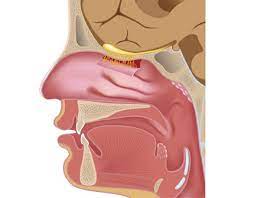

La constitución anatómica de la nariz es fundamental para comprender su estructura y función en el cuerpo humano. Cada uno de los elementos mencionados desempeña un papel específico en la forma y la función de la nariz.

- Esqueleto Nasal: El esqueleto nasal proporciona la estructura y la forma básica de la nariz. Está compuesto principalmente por huesos y cartílagos. Los huesos nasales contribuyen a la forma de la parte superior de la nariz, mientras que el cartílago alar forma la punta y las alas de la nariz. Este esqueleto sostiene los tejidos blandos que recubren la nariz y ayuda a mantener su forma. Además, el esqueleto nasal es crucial para proteger las estructuras internas de la nariz, como el tabique nasal y las cavidades nasales.

- Revestimiento Interno: El revestimiento interno de la nariz, que se encuentra en las cavidades nasales, está formado por una membrana mucosa llamada mucosa nasal. Esta mucosa está revestida de cilios microscópicos y glándulas mucosas que tienen varias funciones importantes. Los cilios atrapan partículas extrañas y las mueven hacia afuera para su eliminación, ayudando a purificar el aire que inhalamos. Las glándulas mucosas secretan moco, que humedece y calienta el aire antes de que llegue a los pulmones. Además, la mucosa nasal es crucial para nuestro sentido del olfato, ya que contiene receptores olfativos que nos permiten percibir los olores.

La constitución anatómica de la nariz es un ejemplo de la complejidad y la importancia de la estructura y función en el cuerpo humano. Cada uno de los elementos mencionados, desde el esqueleto que sostiene la forma hasta el revestimiento interno que purifica y aclimata el aire que respiramos, contribuye a la salud y el funcionamiento adecuado de este órgano vital. Además, la nariz desempeña un papel significativo en la apariencia y la identidad de una persona, lo que la hace aún más fascinante desde una perspectiva anatómica y cultural.